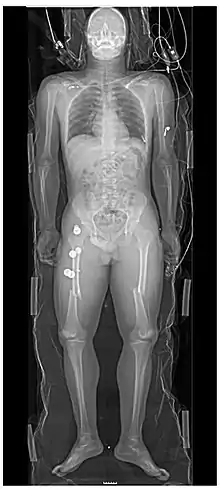

رادیوگرافی پروجکشنی یک نوع رادیوگرافی و تصویربرداری پزشکی است که تصاویر دو بعدی با اشعه ایکس تولید میکند. فراگیری تصویر بهطور کلی توسط رادیوگرافی انجام میشود و تصاویر اغلب توسط رادیولوژیستها مورد بررسی قرار میگیرند. رادیوگرافی ساده بهطور کلی به تصویر برداری رادیوگرافی (بدون استفاده از تکنیکهای پیشرفته مانند توموگرافی کامپیوتری که میتواند تصاویر سه بعدی تولید کند) اشاره دارد. رادیوگرافی ساده میتواند به رادیوگرافی بدون یک عامل رادیو کنتراست یا رادیوگرافی اشاره کند که یک تک تصویر ایستا را تولید میکند، در مقایسه با فلوروسکوپی، که از لحاظ فنی نیز تصویر برداری میشوند.

- بافتهای سخت مانند استخوان نیاز به یک منبع فوتون با انرژی نسبتاً بالا دارند و بهطور معمول یک آند تنگستن با یک ولتاژ بالا (50kVp تا 150kVp) در یک ماشین سه فاز یا فرکانس بالا برای تولید bremsstrahlung یا تابش ترمزی استفاده میشوند. بافت و فلزات استخوانی چگال تر از بافت اطراف هستند و بدین ترتیب با جذب بیشتر فوتونهای اشعه ایکس، مانع جذب این پرتو میشوند.[10] هرکجا که بافت متراکم، اشعه ایکس را جذب کرده یا متوقف کند، فیلم اشعه ایکس حاصل از آن خارج میشود و به نظر میرسد آبی روشن است، در حالی که قسمتهای سیاه این فیلم، بافت چربی، پوست و اندامهای داخلی را نشان میدهد، که نمیتواند اشعه ایکس را متوقف کند. این معمولاً برای دیدن شکستگیهای استخوانی، اشیاء خارجی (مانند قورت دادن سکهها) و مورد استفاده برای پاتولوژی استخوانی مانند ورم مفاصل و استخوانها (آرتروز)، عفونت استخوان، سرطان (استئوسارکوما) و همچنین مطالعات رشد (طول پا، آکندروپلازی (بیماری مادرزادی استخوان که موجب بدهنجاری و کم رشدی اسکلت بدن میشود)، اسکولیوز و …) میباشد.